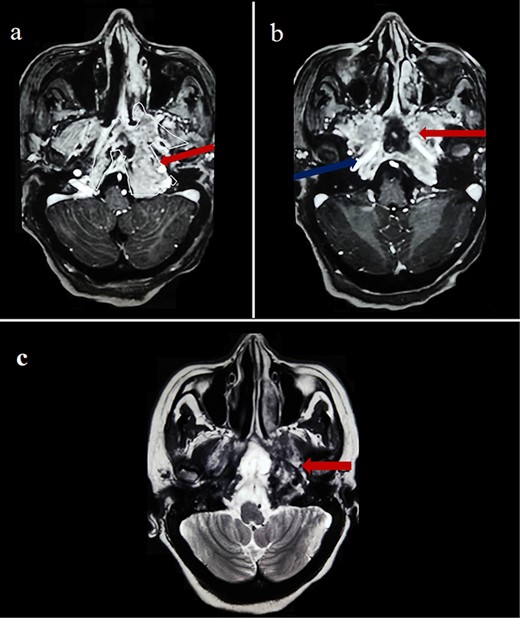

By the end of biological exploration, the patient reported a recurrence of headaches and blurred vision, 2 months after surgical decompression. Cerebral MRI revealed a relapse of the sphenoid plasmacytoma, measuring 70 mm (Fig. 3). Given the pathological diagnostic result, surgical re-intervention was not decided. Instead, the patient was treated with external beam radiotherapy (RTX) focused on the sphenoid bone (30 Gy), followed by immunochemotherapy with zoledronic acid. After 6 months, complete response was noted with the resolution of symptoms, disappearance of the monoclonal band, normalization of sFLC, and persistence of lytic sequelae on cerebral MRI (Fig. 4). Autologous stem cell transplantation (ASCT) was successfully performed, and the patient was put under treatment maintenance. After 18 months of follow-up, clinical, biological, and radiological evaluation confirmed sustained complete remission.

Cerebral MRI (axial views) showing a relapse of the sphenoid BP measuring 70 mm (a, b: T1 weighted post-gadolinium; c: T2 weighted).